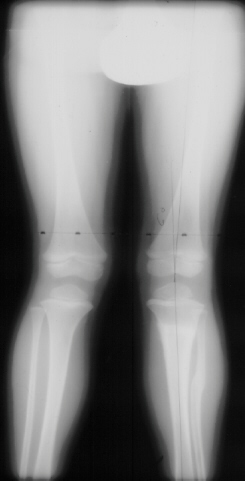

X-ray Set 2. 16 Months post Fracture, Right 8* Left 26* Mechanical axis, Left 34* Femoral Tibial Angle.

At this time the child was experiencing significant pain and inability to ambulate. He was treated with varus producing closing wedge osteotomy of the proximal tibia with neutral alignment